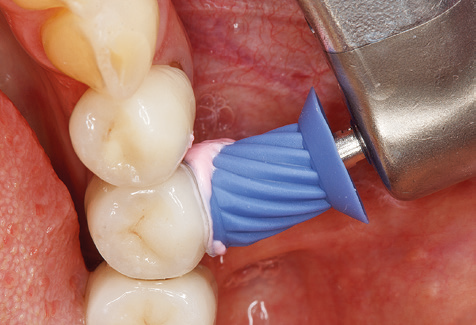

Good illumination of the working field facilitates the process considerably. The system used by the authors achieves this thanks to a 5x LED ring integrated in the handpiece. Naturally, a range of working tips for different indications is also offered. A straight, universally employable tip is the basic instrument required for machine cleaning of natural teeth (Fig. 5a and b). Curved tips, which allow access to exposed furcations, are also available for hard-to-reach areas in the posterior region (Fig. 6).

Of course, working tips for the cleaning of implant surfaces are also indispensable for SPT in patients fitted with implants. The implant cleaning attachment on the system used here is characterised by its tapered, hexagonal design. This design allows light, atraumatic penetration of the peri-implant pocket and displays a good cleaning performance (Fig. 7).

Fig. 9: The accessible implant and tooth surfaces are polished with polishing cups and suitable polishing compounds. – Fig. 10: Repeat instruction in the use of appropriate aids for oral hygiene at home should also form part of SPT. – Fig. 11a and b: Clinical situation 12 years after insertion of the prosthetic restoration. During this period, only a veneering ceramic fracture on tooth 47 and the requirement for endodontic treatment of tooth 12 were observed. All restorations are still functioning as intended.